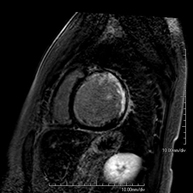

RM Cardíaca con estrés miocárdico

Es una prueba diagnóstica no invasiva, que obtiene información morfológica y funcional del corazón y las estructuras adyacentes. De esta manera, se pueden diagnosticar diferentes patologías congénitas y adquiridas. Durante la prueba, el técnico le pedirá varias veces que aguante la respiración durante 10-15 segundos, para así poder obtener las imágenes lo más claras posible. En la gran mayoría de casos es necesario el uso de contraste intravenoso (gadolinio) para completar el estudio, un tipo de contraste que raramente produce reacciones adversas. Además, se introduce un fármaco (Adenosina) por vía intravenosa, para ejercer sobre el corazón un efecto similar al que se produce durante el ejercicio físico. Se comparan las imágenes obtenidas en reposo y tras el "estrés" farmacológico para detectar déficits de aporte sanguíneo al ventrículo izquierdo del corazón. La duración de la prueba es de aproximadamente 45 - 60 minutos. Es necesario que 24 horas antes de la prueba no tome alimentos que contengan cafeína (café, té, chocolate, bebidas de cola…). Está contraindicada en pacientes con marcapasos, y el paciente debe avisar si es portador de implantes metálicos y/o clips quirúrgicos.